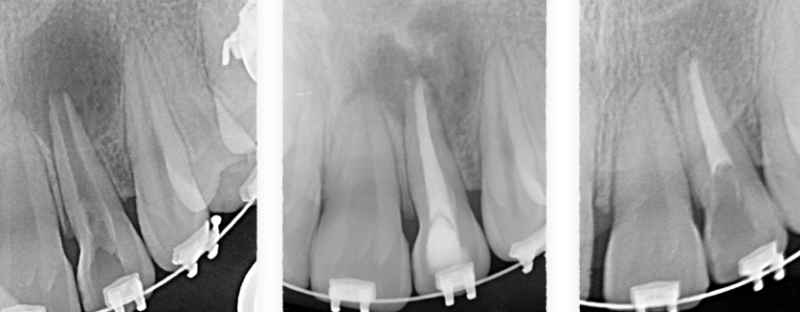

Recuperación ósea

FORMACIÓN DE ENDO-HUESO: IMPORTANCIA DEL PAPEL DE LA ENDODONCIA EN LA REGENERACIÓN DE HUESO. Dr. Borja Zabalegui.